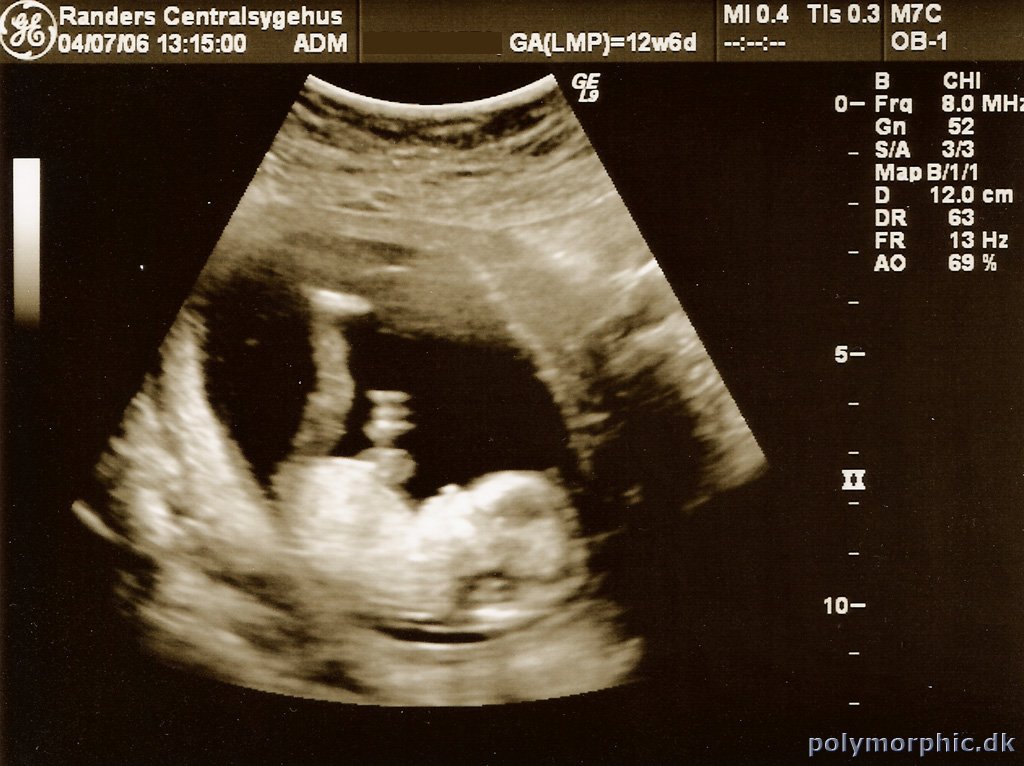

Første scanning

Så har vi være til den første scanning med Bette Bøvs. Alt er lige som det skal være, så vi er sindsygt glade.

Nu venter vi bare på anden scanning så vi forhåbentlig kan få kønnet at vide.

Der er billeder fra scanningen her: